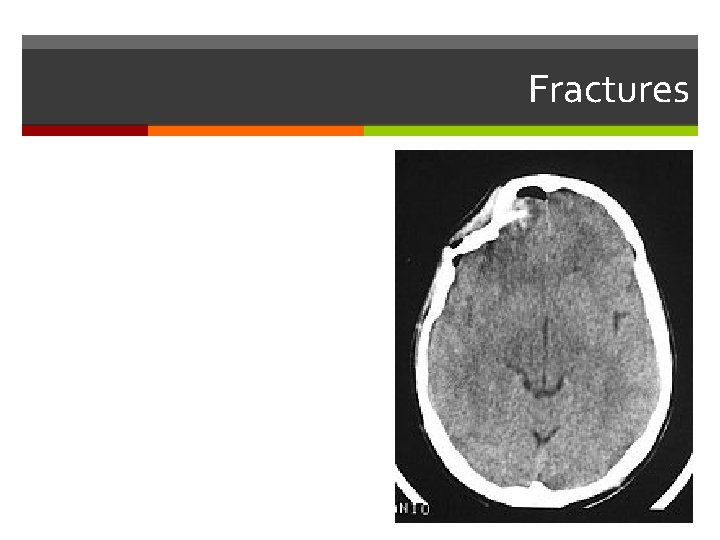

Fractures

Fractures Treated by Reduction: Closed Open